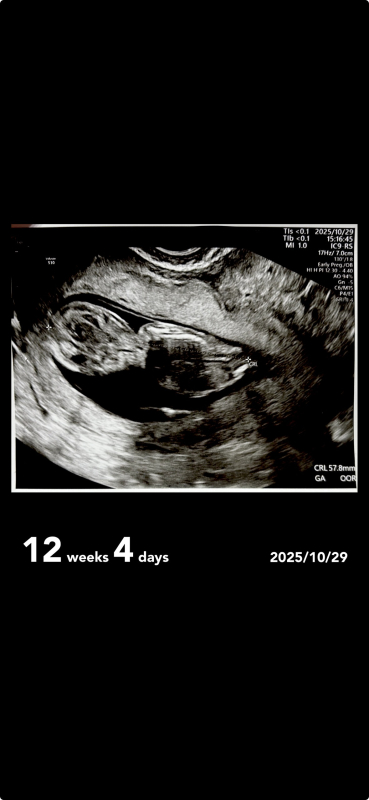

12週エコー

先日エコーを見ていたところ気になったことがあったので質問したいです。

首の後ろのむくみとかで分かるって書いていて、見てもわからなくて、背中の後ろの線はなんなのでしょうか

これは浮腫なんですか??

首の後ろの線は、空洞の部分が大きく、首の浮腫とは考えにくいかなと思います。卵膜など赤ちゃんが包まれている膜かなと思いますが、はっきりとは断言できないので医師に確認してみてください。